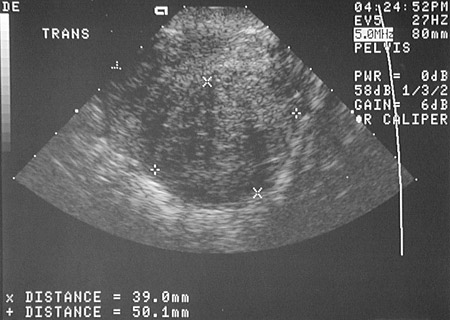

![]() | These pelvic ultrasound views above and below demonstrate a large posterior uterine leiomyoma (marked by the x and + cursors to give the size) measuring 4.6 x 3.9 x 5.0 cm. Note how circumscribed and rounded this tumor mass is. This leiomyoma was large enough to impinge upon the endometrial cavity and cause abnormal bleeding with menometrorrhagia. |